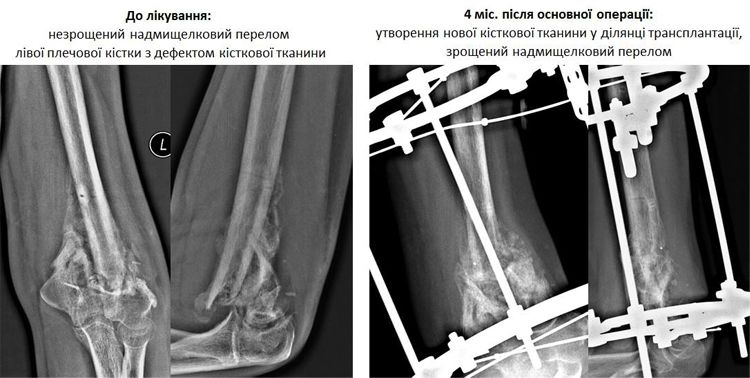

Минулого тижня, через 4 місяці після основного етапу лікування плеча, бійцю було зроблено новий рентгенівський знімок та знято апарат.

На знімку можна добре помітити утворення нової кісткової тканини у місці введення 3D-гелю з чипсами остеопластичного матеріалу та аутологічними стовбуровими клітинами, а також зрощений надмищелковий перелом.

А 26 травня була проведена основна операція – у місце дефекту лівої плечової кістки Євгена був введений 3D-гель з чипсами остеопластичного матеріалу та аутологічними стовбуровими клітинами.